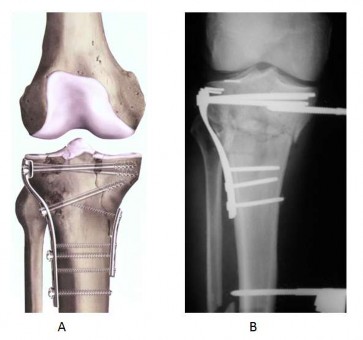

Hình 1.8 Nẹp nhỏ chống trượt (A) hoặc cố định ngoài (B) dùng để thay thế nẹp nâng đỡ ở mâm chày trong.

"Nguồn: Wiss D.A., Watson J.T., Fractures of the proximal tibia and fibula,

Rockwood and Green's fractures in adults, 1996"[123]